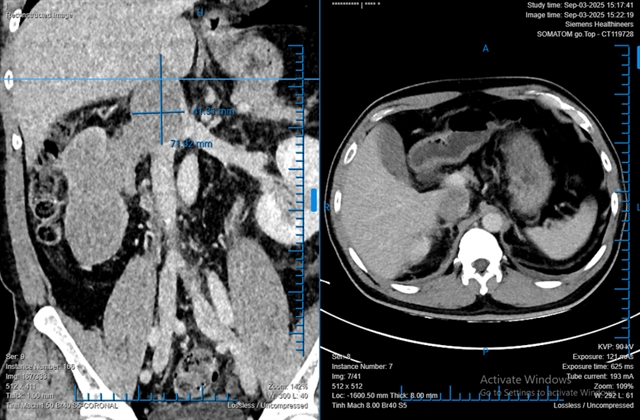

HCM CITY — Doctors at Bình Dân Hospital in HCM City have successfully performed a fully robotic radical nephrectomy to remove a large kidney tumour, with a thrombus extending 76mm into the inferior vena cava (IVC), from a 48-year-old male patient.

The patient, L.T.D., 48, from Quảng Trị Province, was diagnosed with a large right kidney tumour measuring 68 x 86 x 138mm with a thrombus extending into the IVC.

Dr. Phạm Phú Phát, head of Urology A at the hospital, who led the operation, said: “This was the largest tumour thrombus he has ever removed — 76mm in length.